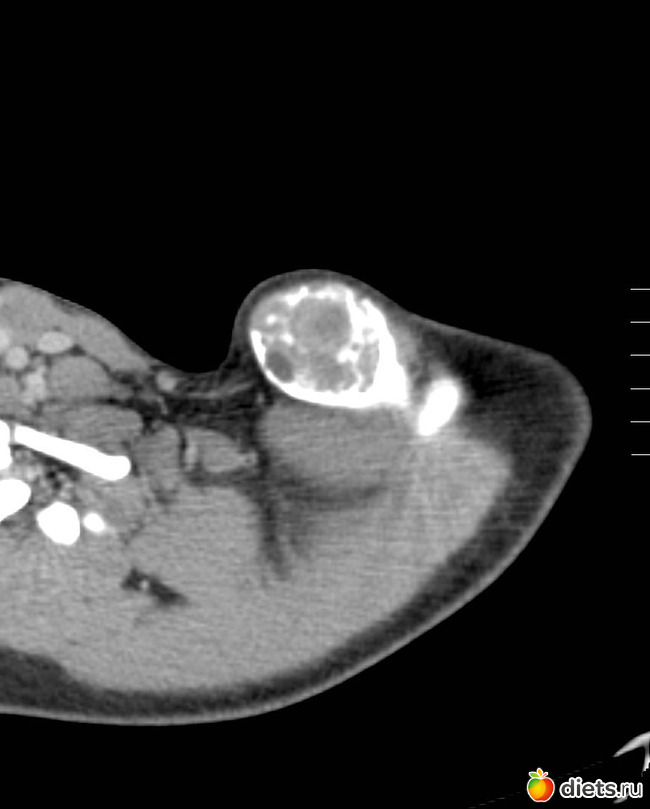

На МРТ врач обнаружил огромную кисту в области ключицы. Киста разрослась настолько, что косточка в ключице была вынуждена выгибаться как может.

Тянуть не буду с результами. Вообщем есть подозрение что это опухоль.

Злокачественная она или нет, пока не могут сказать. В любом случае её будут полностью удалять, вместе с частью сломанной косточки.